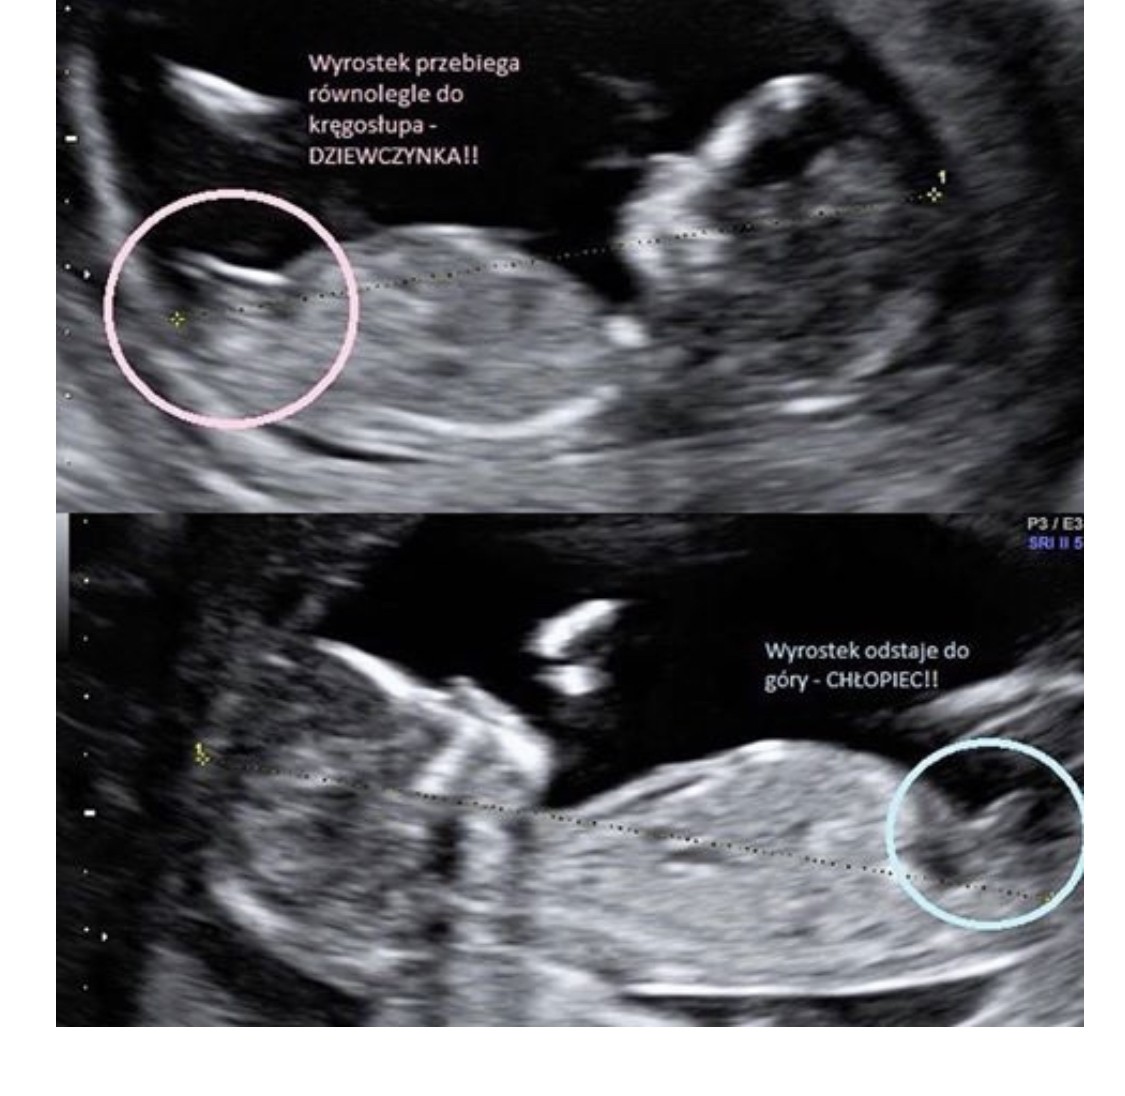

Dziękuję za odpowiedźRaczej dwie równoległe kreski stawiałabym na dzuewczynkę. Za 2 tyg powinno już być dobrze widać![]()

Tez mi się właśnie tak wydawałoWedług mnie dzidzia leży tutaj bokiem i nie widać wyrostka. Także chyba będziesz musiała trochę jeszcze poczekać...rozumiem to bo sama się niecierpliwiepozdrawiam i życzę zdrówka

Muszę sprawdzić w dokumentach dokładnie, a te zostawiłam u teściówGdyby zdjęcie było z boczku zrobione to tak jak dziewczyny powyżej mówiły - wyrostek układa się przy chłopcu wzwyż, a przy dziewczynce bardziej rownolegle. Masz może inne zdjęcie?

No to sprawdź i na spokojnie może będziemy "czarować".Muszę sprawdzić w dokumentach dokładnie, a te zostawiłam u teściów![]()